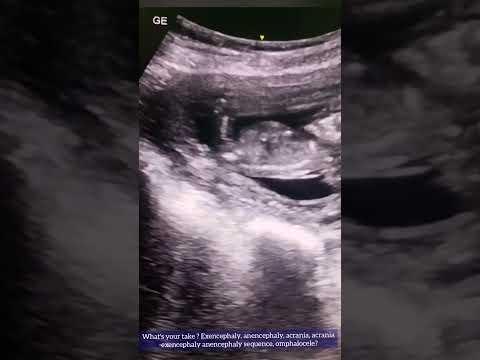

Acrania exencephaly anencephaly sequence ultrasound